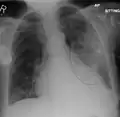

- Normal AP CXR

- Normal lateral CXR

- AP CXR showing left lower lobe pneumonia associated with a small left sided pleural effusion

- AP CXR showing right lower lobe pneumonia

- AP CXR showing pneumonia of the lingula of the left lung

- Right upper lobe pneumonia as marked by the circle.

- Left upper lobe pneumonia with a small pleural effusion.

- Right lower lobe pneumonia as seen on a lateral CXR